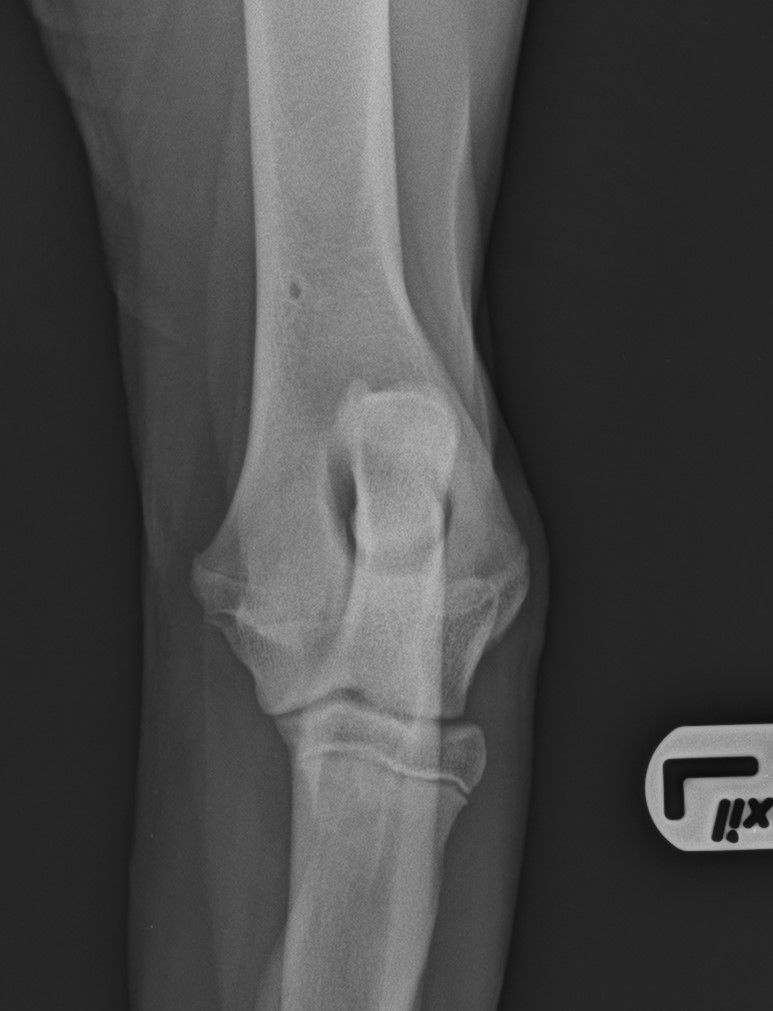

esame radiografico per displasia di anche e gomiti

DISPLASIA DELL'ANCA E GOMITO

La displasia dell'anca e del gomito sono malattie ereditarie che colpiscono i cani durante la crescita, causate da fattori genetici, ambientali, nutrizionali e traumatici, che alterano lo sviluppo articolare e portano a dolore, limitazione e artrosi.